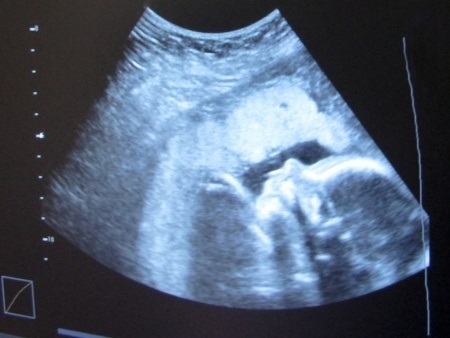

התביעה עוסקת בעיקרה בבדיקת שקיפות עורפית שאליה הגיעו ההורים – בדיקת אולטראסאונד שנעשית בשלב מוקדם יחסית של ההריון, ובה מודדים את הרווח שבין העור והצוואר של העובר שנובע מהצטברות נוזל באזור הצוואר. הבדיקה מאפשרת לאבחן חשד בסבירות גבוהה לתסמונת דאון.

התביעה טענה כי המדידות שביצעה רופאה מטעם הקופה לא בוצעו בהתאם להוראות משרד הבריאות. הטענה מבוססת על כך שב-3 מתוך 4 התמונות שצולמו בבדיקה, העובר כלל לא נמצא במנח שמאפשר מדידה של שקיפות העורף. הגם שבתמונה הרביעית נראה כי התאפשרה מדידה – אין אף עדות לביצוע מדידה במשך כל הבדיקה.